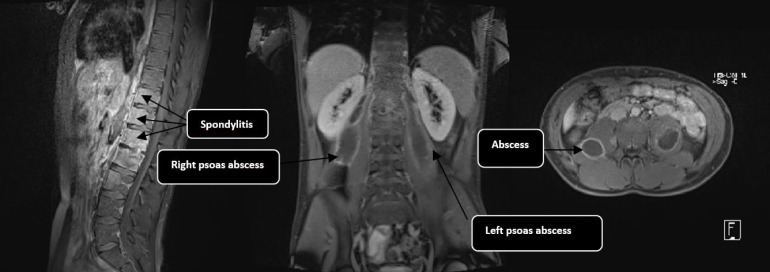

Psoas abscess is a rare infection historically associated with tuberculosis (TB), although non-tuberculous bacterial causes, particularly Staphylococcus aureus, have become increasingly common. This type of abscess can be either primary or secondary, and its diagnosis remains challenging due to the non-specific nature of clinical signs. Imaging and microbiological analyses are essential for establishing the diagnosis. We report the case of a 22-year-old patient with no significant medical history, who presented with persistent mechanical low back pain for 18 months. Initial computed tomography revealed a non-compressive disc protrusion, leading to treatment with non-steroidal anti-inflammatory drugs, without improvement. Further investigations revealed an extrapulmonary spinal localization of TB in an immunocompetent patient, with bilateral psoas abscesses caused by Mycobacterium tuberculosis, confirmed by the Ziehl-Neelsen staining, auramine staining, culture on Löwenstein-Jensen medium and GeneXpert PCR. Anti-TB treatment was initiated, resulting in favourable clinical evolution.